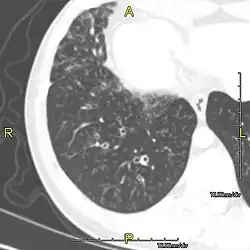

CT image showing dilated and thickened medium-sized airways (bronchiectasis) in a patient with Kartagener syndrome